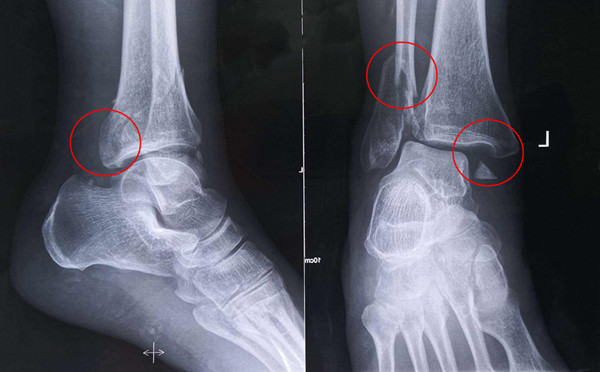

踝關節(jié)骨折在X影像上的表現(xiàn)有很多種。如內踝骨折和外踝骨折,我們可以在影像上看到骨折處的骨折線是不連續(xù)的。還有后踝的骨折,內踝、外踝、后踝聯(lián)合在一起發(fā)生的骨折,我們稱之為“三踝骨折”,這些都是在X影像上能夠顯示出來的。

內踝骨折

外踝骨折

后踝骨折

三踝骨折